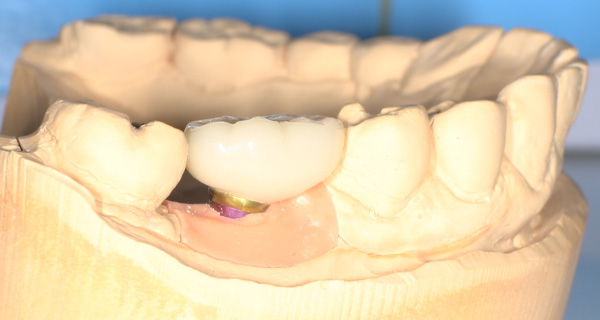

インプラント手術を行いました。

手術の時に使用するサージカルステント

レントゲン画像 -

インプラント手術から3ヵ月後、型どりをして、仮歯を製作しました。

仮歯の調整期間を経て、セラミックの歯が入りました。

レントゲン画像 治療前 インプラント治療後